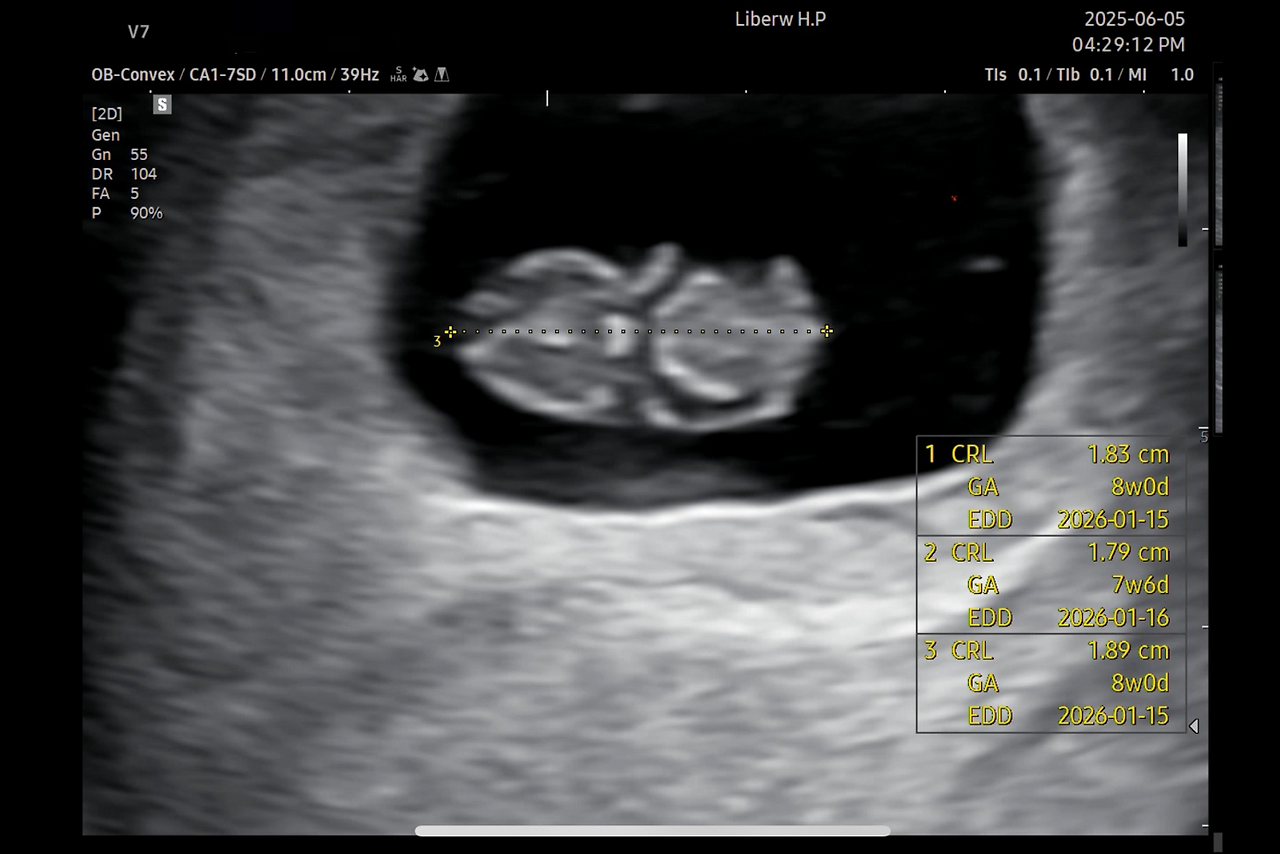

콩딱거리는 심장뿐이던 콩알 모양 아기가 팔다리와 꼬리까지 꼬물거리는 젤리곰 아기가 되었다. 2주 동안 0.5cm 에서 1.8cm로 폭풍성장한 것. ‘아 이게 팔이군요’ 바로 알아차렸다면 더 좋았겠지만 나도 엄마는 처음인지라, 의사 선생님이 가리키며 설명해 줄 때까지 요 땅콩은 뭣인가 했다. 알고 보면 너무나도 선명한 머리와 팔과 다리인데 말이다!

처음으로 복부 초음파를 했다. 아프지 않고 편해서 좋다.

출산 예정일이 확정되었다. 이모 삼촌들, 모두 캘린더에 저장해 주세요!